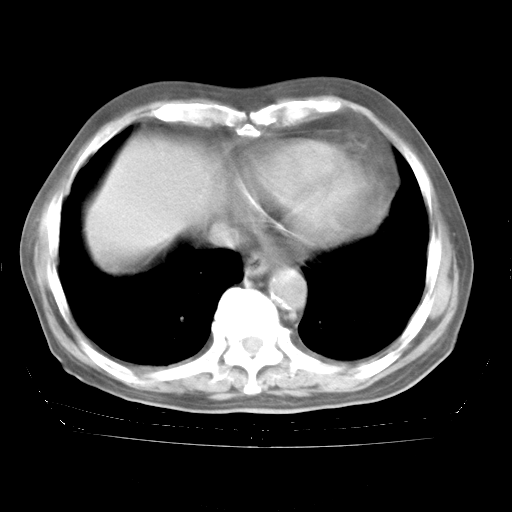

4月28日肺部CT

1、108#的是4月14日的胸部CT(发此贴时还没看着28日的CT)。14日的胸部CT其实已经出现改变(如108#所述),个人认为28日的胸部CT除纵膈窗疑似有双侧胸膜增厚或少量胸积液(可行胸部B超明确)外,与4月14日对照病变有所加重;2、已经给予“异烟肼、利福平、乙胺丁醇”抗痨治疗?如果是,甲强龙80mg可缓慢减量;如果环磷酰胺已停用,暂不使用;3、中性粒细胞92%,明显升高,目前体温情况?注意合并细菌感染可能,使用左氧氟沙星情况下,是否联用B-内酰胺类抗菌药物?另外是查免疫全套非风湿全套。

今请临免主任会诊后认为:4月14日胸部CT已有双下肺间质性改变。患者病情复发多系激素减量过快不正规所致。目前甲强龙80mg/日,一周后酌情开始减量,不易过快。环磷酰胺若已停用,暂不使用。他同意目前抗菌药物使用,但应考虑是否加用B-内酰胺类抗菌药物(中性细胞明显增高);2、结核复发目前依据不足;3、若免疫全套各项指标正常,考虑多系特发性肺间质炎可能大。4、加强支持,并注意保护胃黏膜。